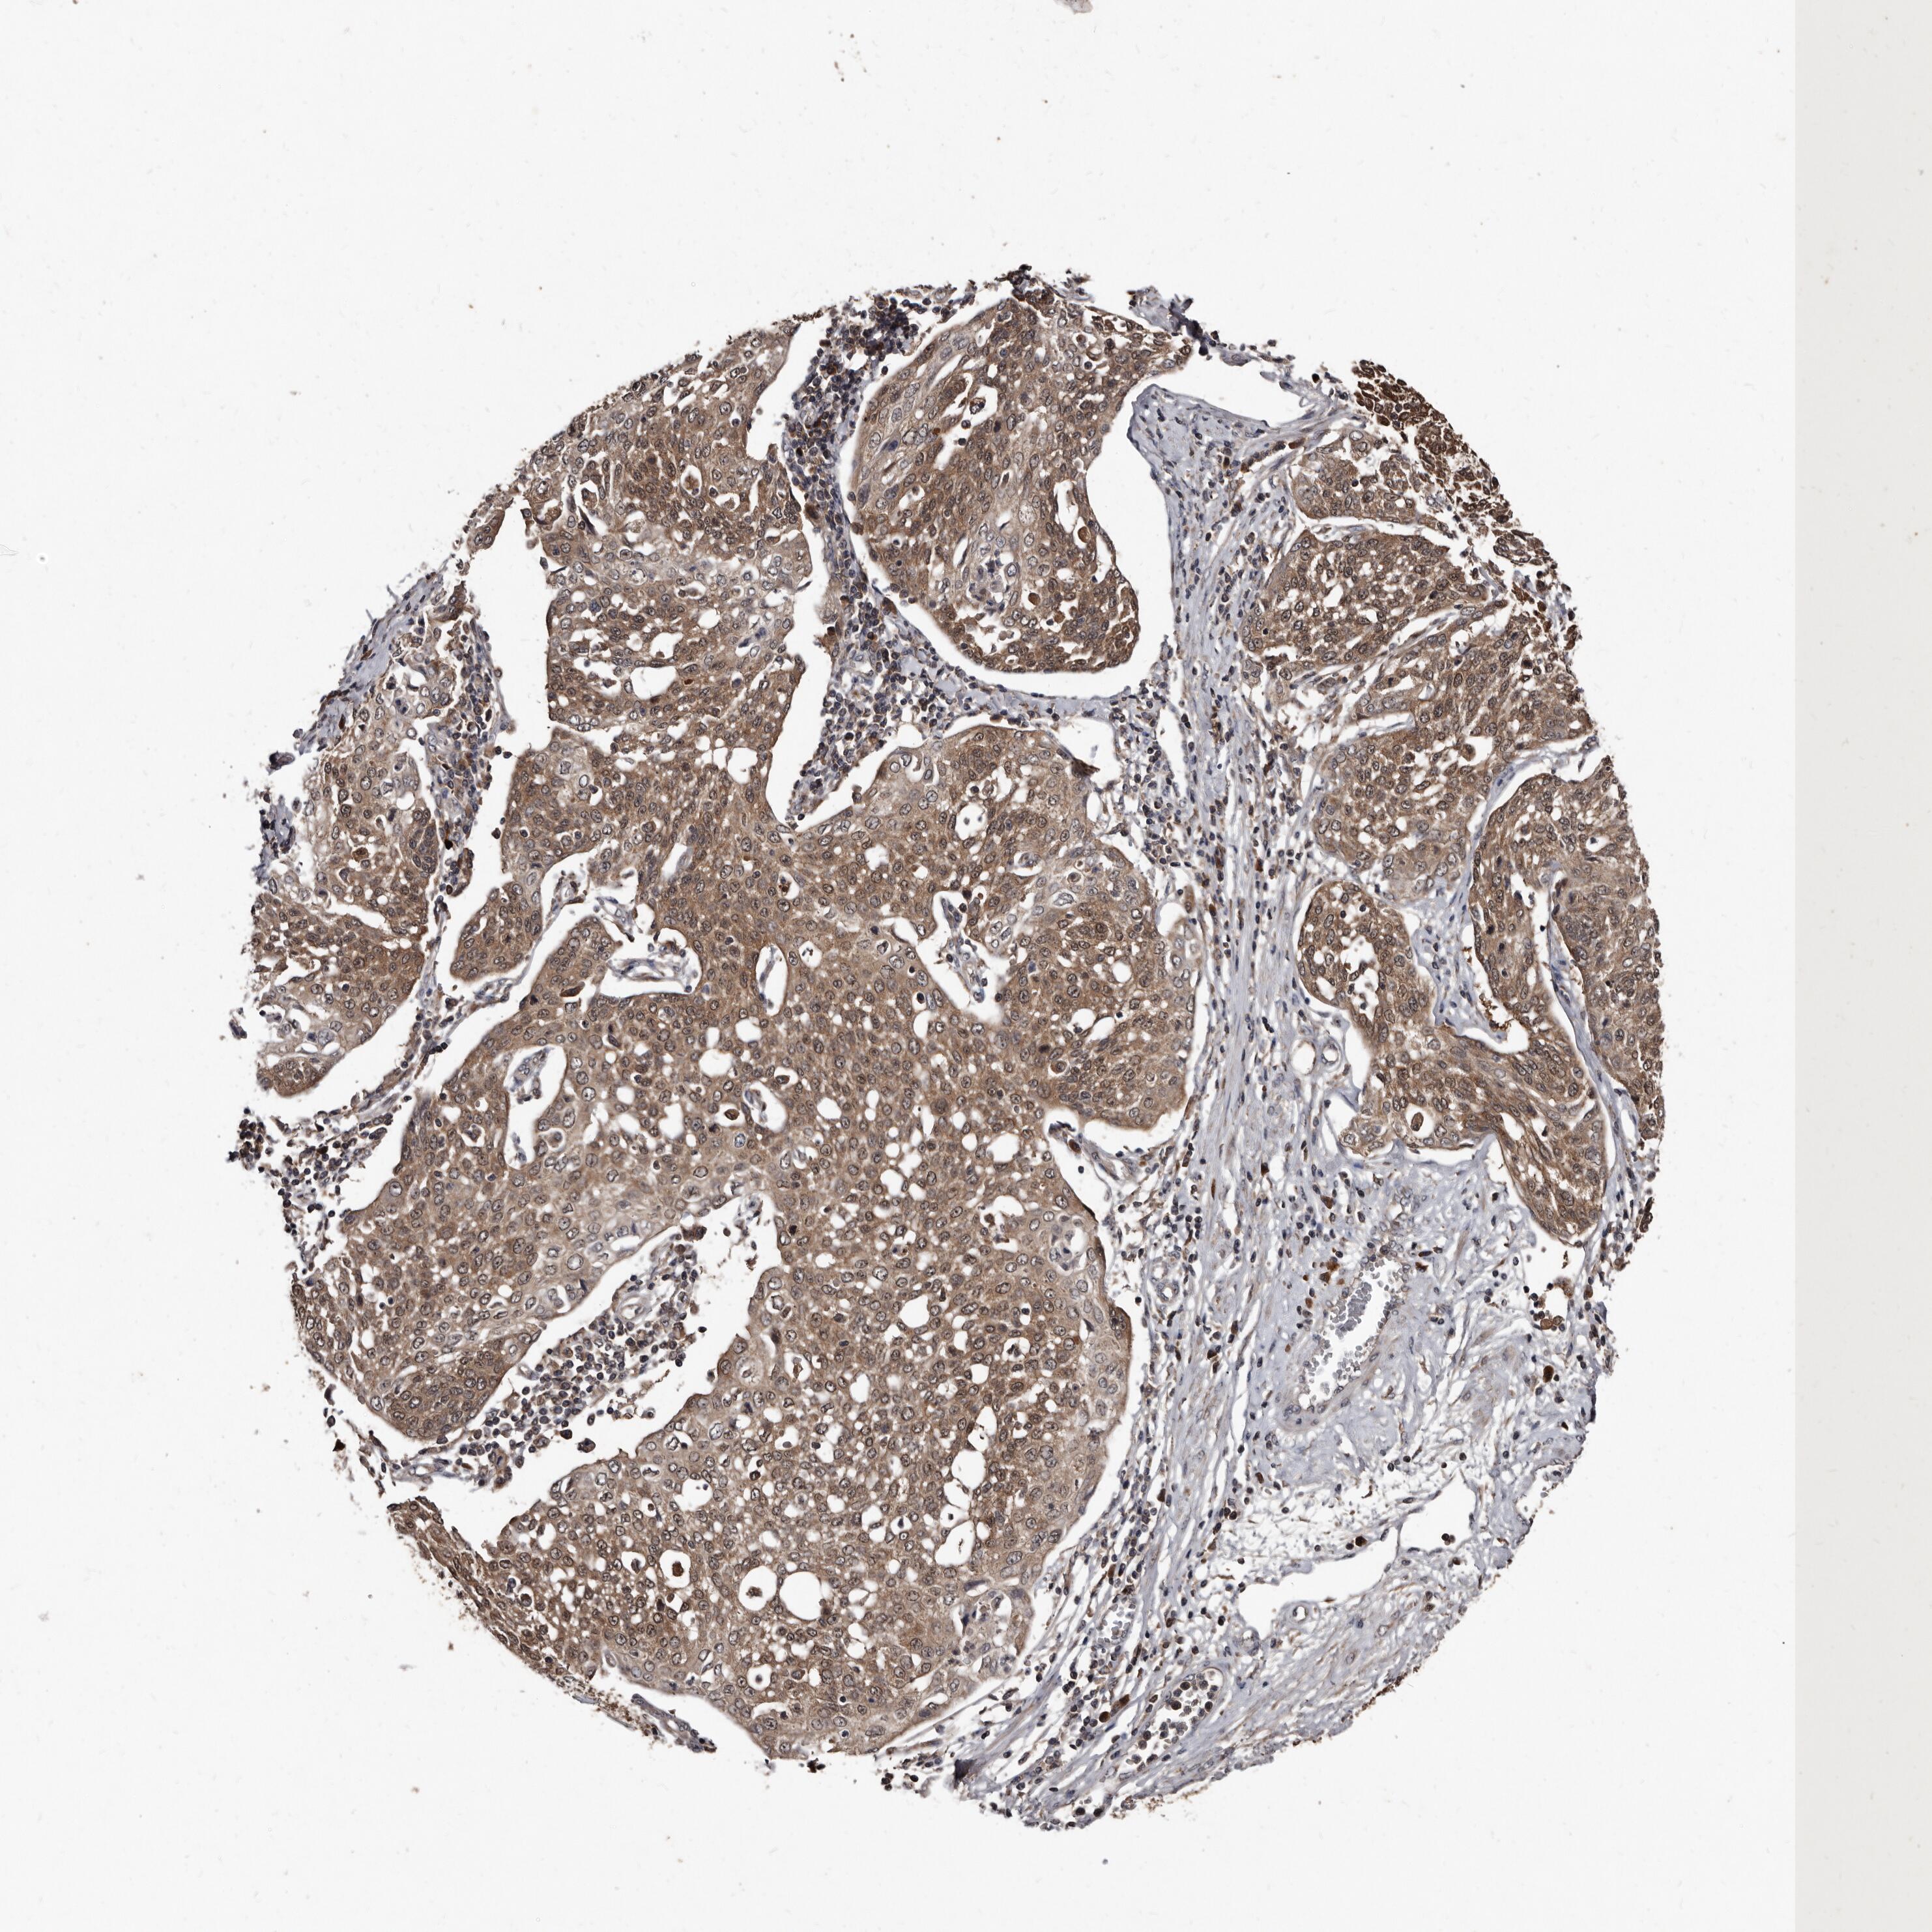

CERVICAL CANCER - Protein expressioni

A mouse-over function shows sample information and annotation data. Click on an image to view it in a full screen mode. Samples can be filtered based on level of antibody staining by selecting one or several of the following categories: high, medium, low and not detected. The assay and annotation is described here.

Note that samples used for immunohistochemistry by the Human Protein Atlas do not correspond to samples in the TCGA dataset.

Antibody stainingi

Antibody staining in the annotated cell types in the current human tissue is reported as not detected, low, medium, or high, based on conventional immunohistochemistry profiling in selected tissues. This score is based on the combination of the staining intensity and fraction of stained cells.

Each image is clickable and will lead to virtual microscopy that enables deeper exploration of all samples and also displays staining intensity scores, fraction scores and subcellular localization as well as patient and tissue information for each sample.

Antibody HPA029900

Staining

High

Medium

Low

Not detected

Intensity

Strong

Moderate

Weak

Negative

Quantity

>75%

75%-25%

<25%

None

Location

Nuclear

Cytoplasmic/membranous

Cytoplasmic/membranous,nuclear

Squamous cell carcinoma, NOS

Adenocarcinoma, NOS